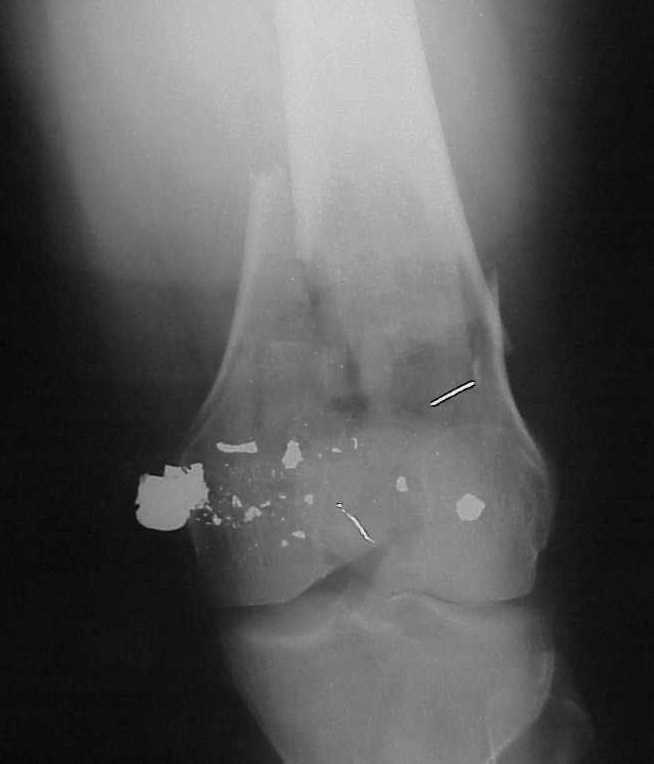

A CT and knee xrays would help identify lateral condyle comminution and/or a "hoffa fragment" of the posterior condyle. I am concerned that the lateral cortex is not sufficient to give purchase for a retrograde IMN. blocking screws could improve this as a possibility. A long blade or LISS if avaible would be my secondary choices. Good luck. Any chance you can get these cases transferred earlier when it

Lateral condyle looks too small for the blade, and the plate too short.

place one anterior to where IMN will go if anterior cortex if insufficient and AP screws on either side of the IMN out of the trochlea to provide some additional varus/valgus stability. I worry about the leg going into valgus w/the lack of lateral cortex.